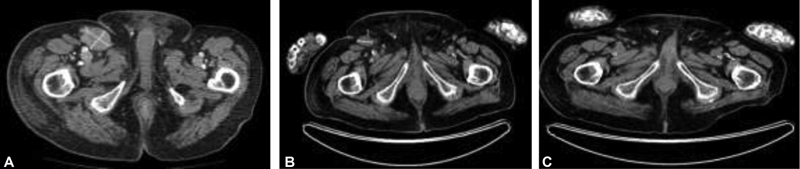

|?Fig. 1Computed tomography (CT) showing (A) right pelvic lymphadenopathy at diagnosis in July 2017; (B) positron emission tomography computed tomography (PET/CT) restaging September 2017 postradiotherapy showing a partial response; (C) PET/CT September 2018 showing a complete response to avelumab.

He was treated with palliative radiotherapy to his right pelvis and groin, receiving a total dose of 28 Gray (Gy) in eight fractions. A positron emission tomography/computerized tomography (PET/CT) scan 6 weeks later in September 2017 demonstrated a partial response to treatment. In October 2017, he received avelumab at a dose of 10?mg/kg 2-weekly via the Merck Patient Access Scheme. His ECOG (Eastern Cooperative Oncology Group) performance status was 2 but improved to 1 with the ongoing response. The patient was followed clinically every 2 weeks with a blood test and physical examination of his edematous right leg.

The PET/CT performed 11 months later in September 2018 showed a complete metabolic response to avelumab ([Fig. 1]). As of January 2021, the patient remained in clinical remission and continued on avelumab that he was tolerating well without any toxicity. Unfortunately, he had a mechanical fall in February 2021 and sustained a subdural hemorrhage (on CT scanning) and died peacefully at the age of 99.